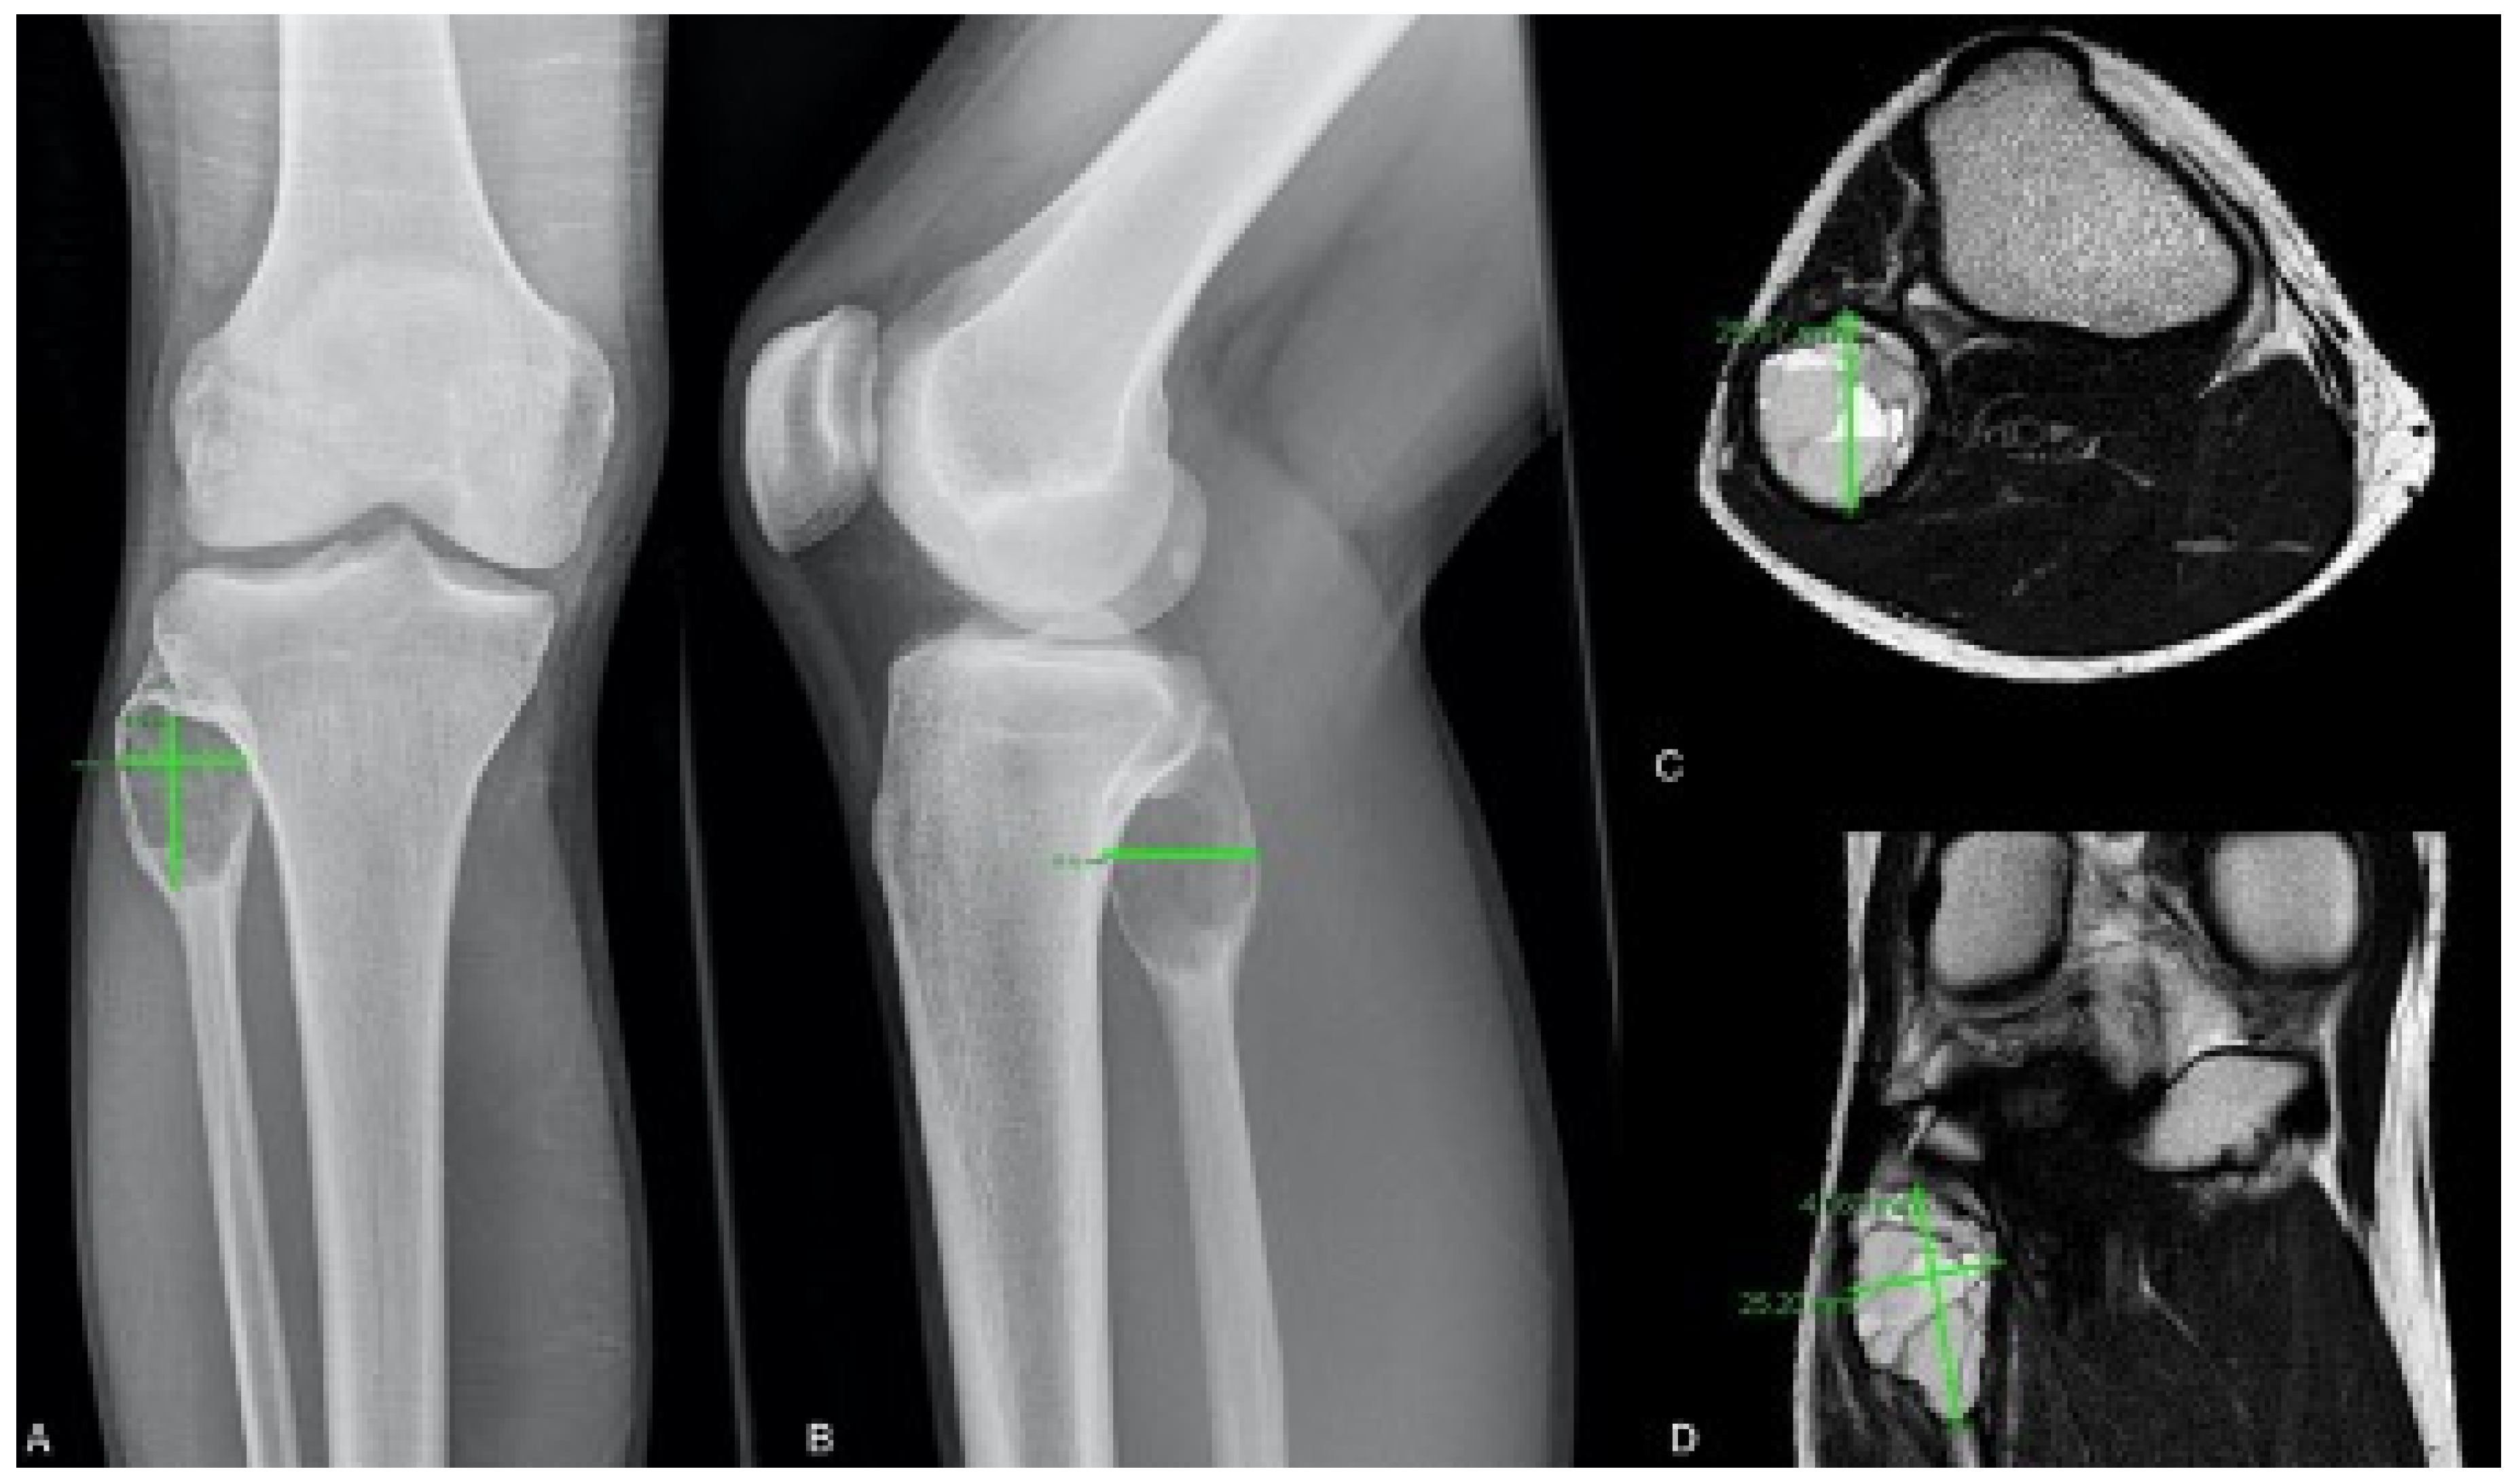

2.1. Radiological Classification and Measurement

3.1. Cyst Volume Measurement

| Patient ID | MRI Volume (cm3) | Radiographic Volume (cm3) | Difference | Localization |

|---|---|---|---|---|

| 1. | 18.5 | 8.55 | 9.95 | Tibia |

| 2. | 38.67 | 22.45 | 16.22 | Humerus |

| 3. | 4.96 | 3.26 | 1.7 | Tibia |

| 10. | 17.64 | 4.10 | 13.57 | Foot |

| 11. | 77.28 | 63.46 | 13.82 | Tibia |

| 12. | 34.35 | 10.64 | 23.71 | Femur |

| 13. | 31.85 | 6.20 | 25.65 | Foot |

| 16. | 54.83 | 38.61 | 16.22 | Humerus |

| 19. | 13.87 | 9.59 | 4.28 | Ulna |

| 21. | 105.33 | 55.53 | 49.80 | Humerus |

| 26. | 29.41 | 17.96 | 11.53 | Tibia |

| 27. | 11.24 | 6.27 | 4.97 | Foot |

| 31. | 6.67 | 1.25 | 5.42 | Ulna |

| 32. | 263.71 | 184.58 | 79.13 | Femur |

| 39. | 21.59 | 3.86 | 17.73 | Humerus |

| 43. | 2.60 | 1.49 | 1.11 | Femur |

| 45. | 31.77 | 17.43 | 14.34 | Humerus |

| 50. | 1.12 | 0.93 | 0.17 | Foot |

| 51. | 16.47 | 10.45 | 6.02 | Fibula |

| 52. | 10.82 | 17.09 | −6.27 | Humerus |

| 54. | 56.50 | 26.80 | 29.70 | Femur |

| 55. | 35.08 | 8.25 | 26.83 | Tibia |

| 67. | 16.56 | 17.47 | −0.91 | Tibia |

| 74. | 11.87 | 4.13 | 7.74 | Spine |

| 75. | 5.42 | 1.48 | 3.94 | Spine |

| 76. | 227.64 | 167.19 | 60.45 | Femur |

| Mean | 44.07 | 27.27 | 16.8 |